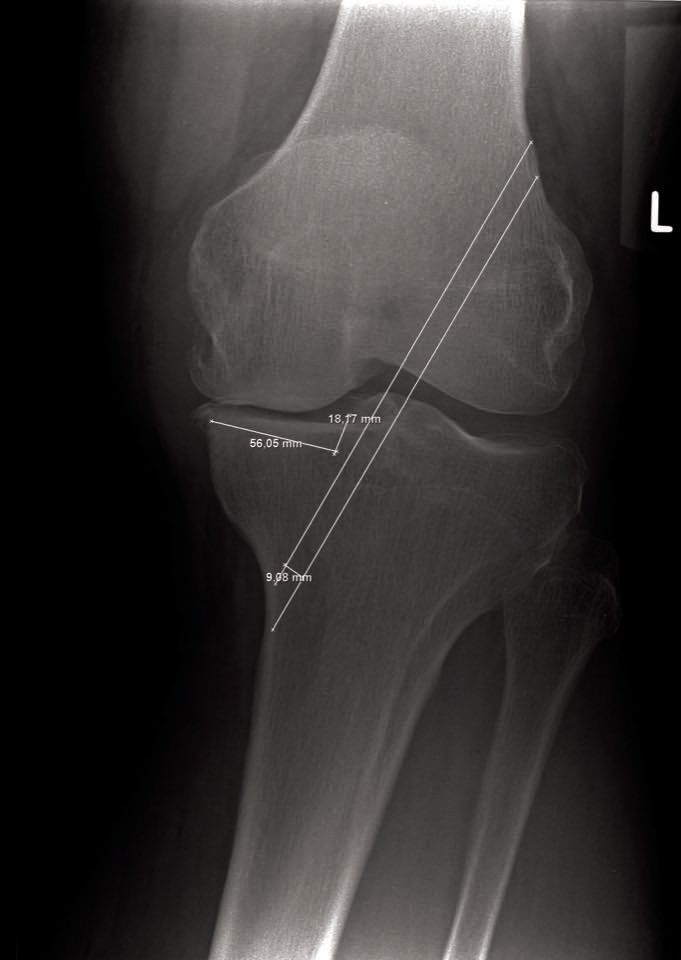

Technique Comment je réalise une prothèse unicompartimentale latérale du genou à plateau fixe , Anders Troelsen Hôpital Universitaire de Hvidovre, Copenhague, Danemark N°270 - Janvier 2018 ● 12 min de lecture